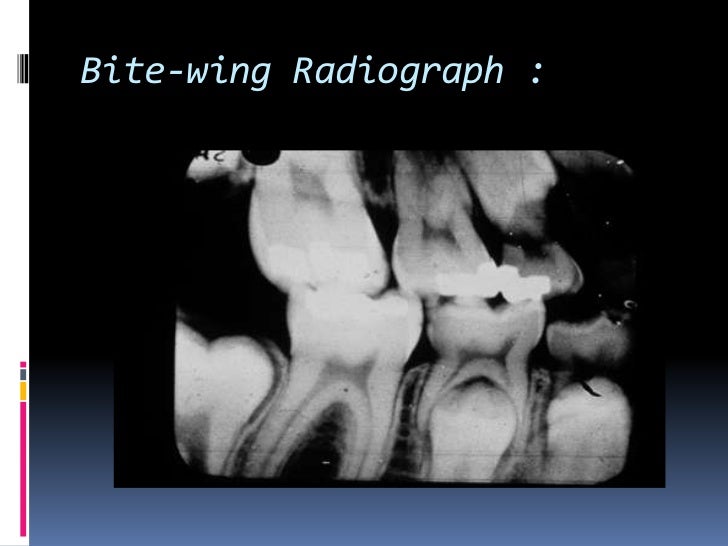

Types Of Radiographs In Dentistry . This article provides the fundamentals of. radiographic imaging is an integral part of the diagnostic process in clinical dentistry. Dental radiographs can broadly be divided in to.